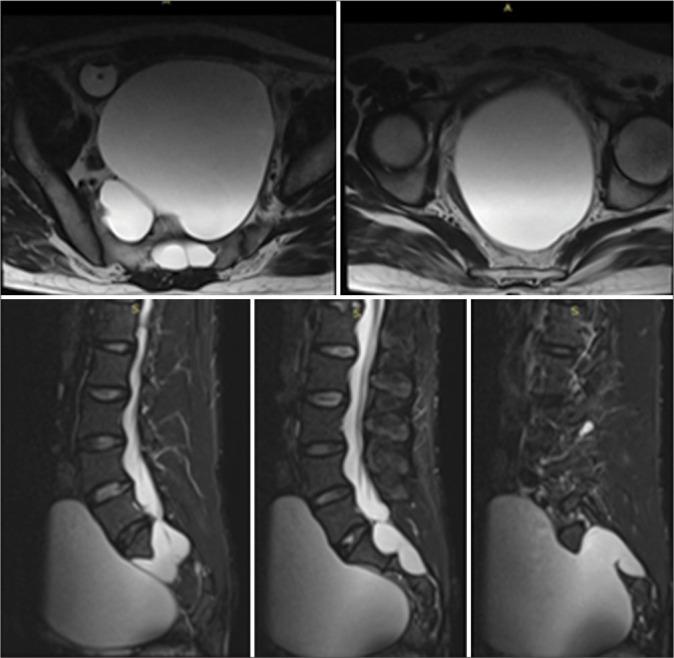

A 30-year-old male presented with a very large magnetic resonance-documented Tarlov cyst (Nabors Type 2) arising from bilateral S2 nerve root sheaths with marked pelvic extension. Although he was initially treated with a S1, S2 laminectomy, closure of the dural defect, and excision/marsupialization of the cyst, he later required placement of a thecoperitoneal shunt (TP shunt).

一名30岁男性,磁共振成像证实存在一个非常大的塔尔洛夫囊肿(纳伯斯2型),起源于双侧S2神经根鞘,并有明显的盆腔延伸。尽管他最初接受了S1、S2椎板切除术、硬脑膜缺损闭合以及囊肿切除/袋形缝合术,但后来仍需要放置脑脊膜腹膜分流管(TP分流管)。